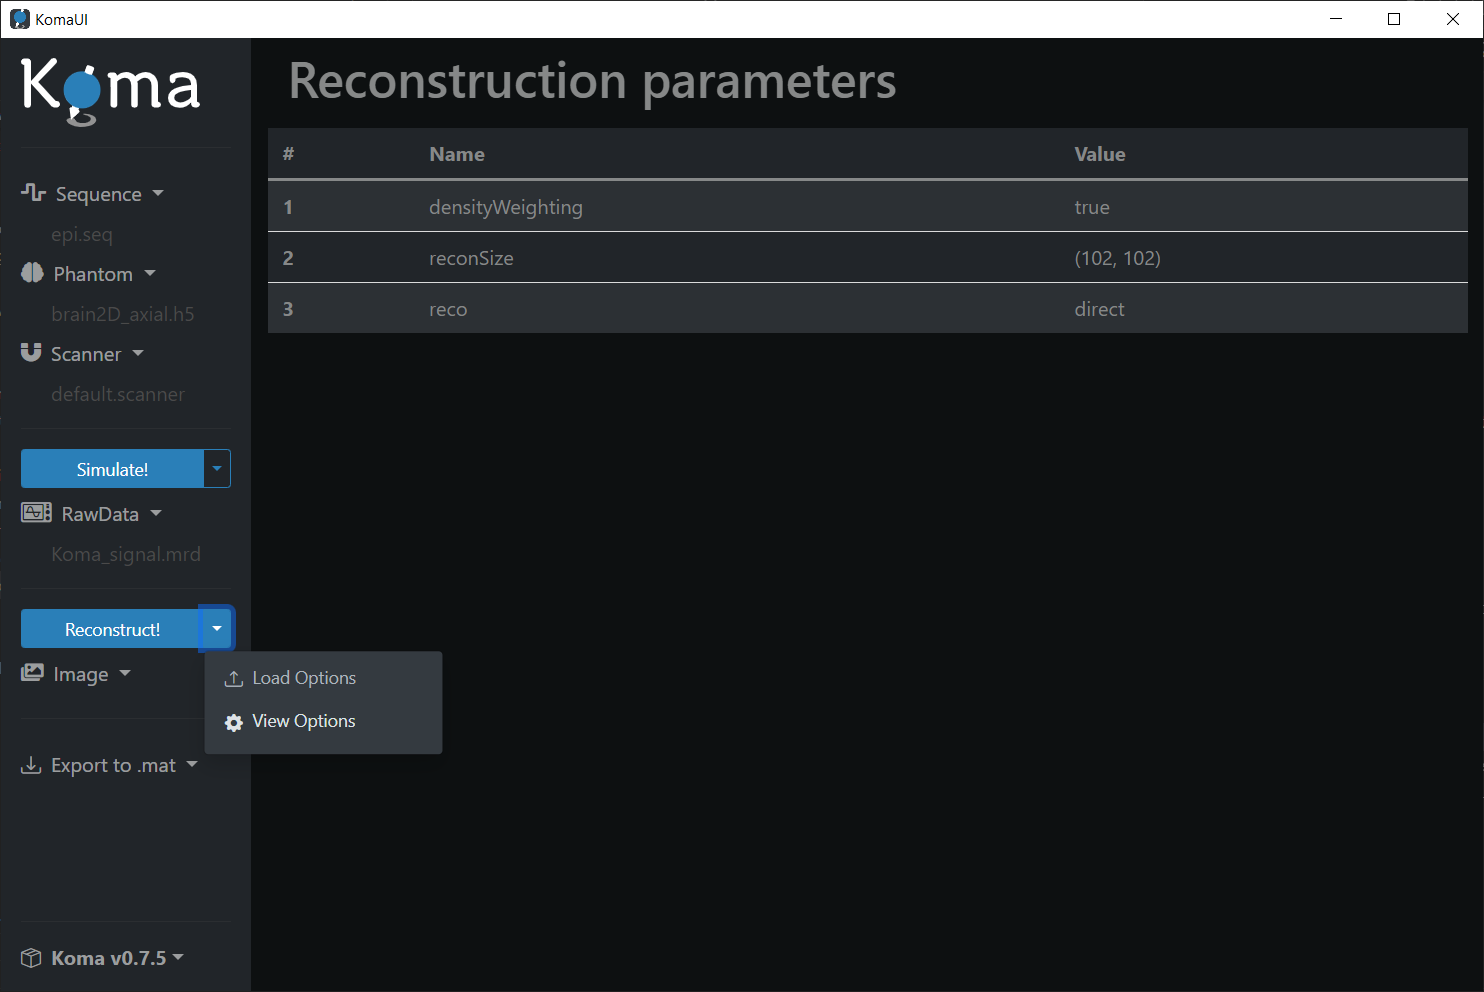

Reconstruction Parameters

To visualize the default reconstruction parameters, click on the Reconstruct! dropdown and then press the View Options button: